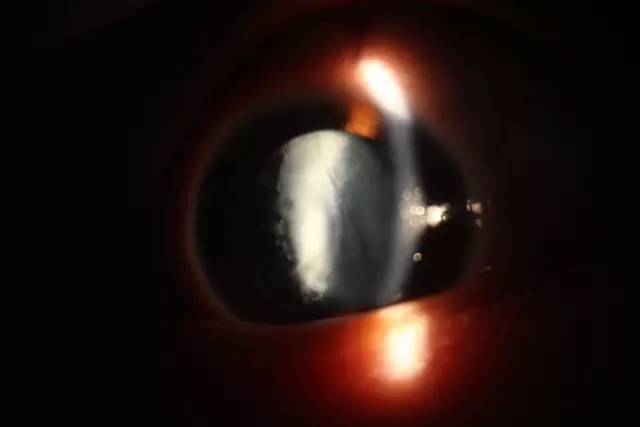

“这个孩子当时来的时候双眼视力极差,眼前有手动,学习和生活都没法正常进行。在进行详细检查后,发现欣欣右眼先天性高度近视,左眼先天性白内障并继发性青光眼,左眼必须进行手术才有改善视力的可能性,便跟孩子家属沟通,决定为她进行手术治疗”。眼科主任牟琳副教授讲道。

术前

术后

由于欣欣的左眼白内障特殊性,今年2月,西南医科大学附属中医医院眼科主任牟琳副教授带领科室团队为欣欣进行了左眼第一次手术,左眼白内障抽吸联合前段玻切术,7月18日再次为其进行了左眼人工晶状体植入术。手术顺利,目前欣欣裸眼视力已达到了0.3左右。手术后,眼科专家团队还给欣欣制定了后期弱视训练的方案。